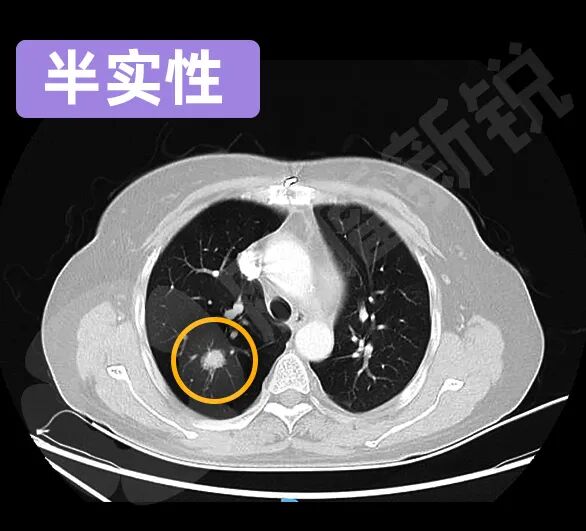

根据磨玻璃结节所包含的实性成分的不同,又可以分为纯GGO、混杂GGO、半实性GGO等不同亚型。

半实性GGO在影像上显示为实性特征,但外围包裹一圈云雾状的图像。